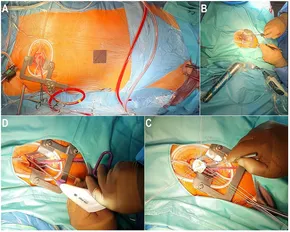

Minimally Invasive Cardiac Surgery (MICS)-CABG - Yashoda, Dr M M YUSUF || One among the few minimally invasive and,

Dr M M YUSUF || One among the few minimally invasive and, fcvm-09-1053572-g001.jpg,

fcvm-09-1053572-g001.jpg,洋書、外国語書籍 Burgen in Deutschland. Troll, Thaddaeus.